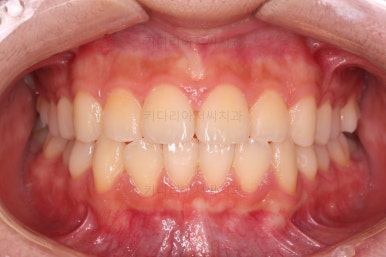

초진 시의 다른 부위들 사진입니다.

약간의 주걱턱 느낌에 약간의 돌출감, 전반적인 치열의 가지런한 느낌은 나쁘진 않았지만 약간의 불량한 교합상태였어요.

다른 부분은 크게 바꾸지 말고 약간의 교합 조절과 어금니 치료에 초점을 맞춰서 교정치료 계획을 잡았습니다.

전후사진을 비교해 볼게요.

약간의 주걱턱, 돌출입은 고칠 의사가 없어서 그대로 유지하였고 주걱턱 패턴으로 인한 부정교합 부분을 개선했으며 무엇보다 중요한 것은 쓰러져서 많이 썩어있던 치아를 자칫 치료 못할 뻔 했는데 교정치료와 병행하여 훌륭하게 치료를 하여 살려 썼다는 점입니다.